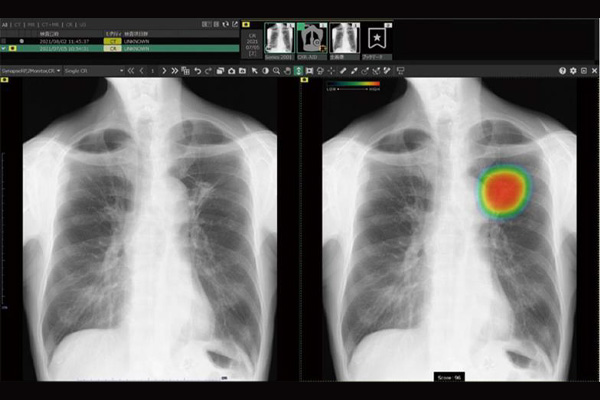

レントゲン撮影装置 エックス線を体に当てることで健康診断以外にも息切れ、呼吸困難の方に肺炎の有無や、心臓疾患の方では心臓の拡大、胸水、肺うっ血を評価します。 -

FUJIFILMの胸部レントゲン画像のAI読影支援システムを2025年より導入しました。 AI導入によるメリットとしては、健診・診療時の胸部単純X線画像診断を支援することで病気の見逃しの防止、早期発見に繋がります。